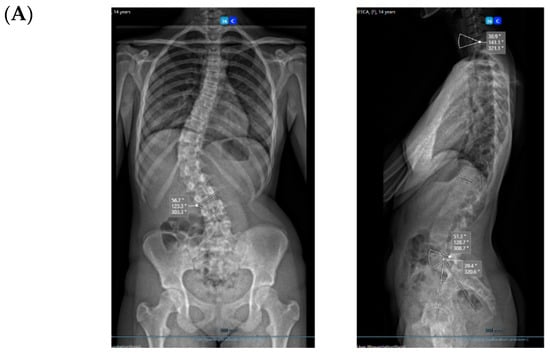

All three cases were thoracolumbar scoliosis (Lenke 5C) with an apex between T12 and L1 (Figure 3, Figure 4 and Figure 5).

Figure 3.

A 14-year-old adolescent. (A) Pre-op. (B) Immediate post-op. (C) One-year follow up.